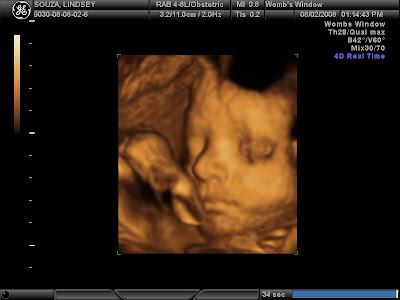

He was asleep when she started the scan but only took a moment to wake right up. And begin poking and jabbing and kicking at the pressure of the ultrasound wand thing. After about 30-35 minutes of being in perfect position for pictures and us seeing his face, he promptly rolled over to face my back then she REALLY had to work to get shots of him, including asking me to eat candy (Travis got a piece too). He was set on being stubborn though and wouldn't flip back over so after about 10 minutes of seeing what we could like he was, we called it a day. It was only supposed to be 30 minutes so I had no complaints. He kept his hands up around his face. Sometimes over it, sometimes just in front of it. Occasionally a foot would pop up there also. As you'll see in the pictures, he would OPEN HIS EYES some too. Travis really liked that. All in all, we were all amazed and it was worth every cent to do it. I wanted to put some of the dvd on here, but ummm, video conversion isn't my strong point and I've already got 1 email asking where are the pictures, so I'm just going to put them up here for now! Here are my favorites:

Bringing up the arms

This was only a few minutes before he flipped over. He looks like he's had enough doesn't he? Poor thing.